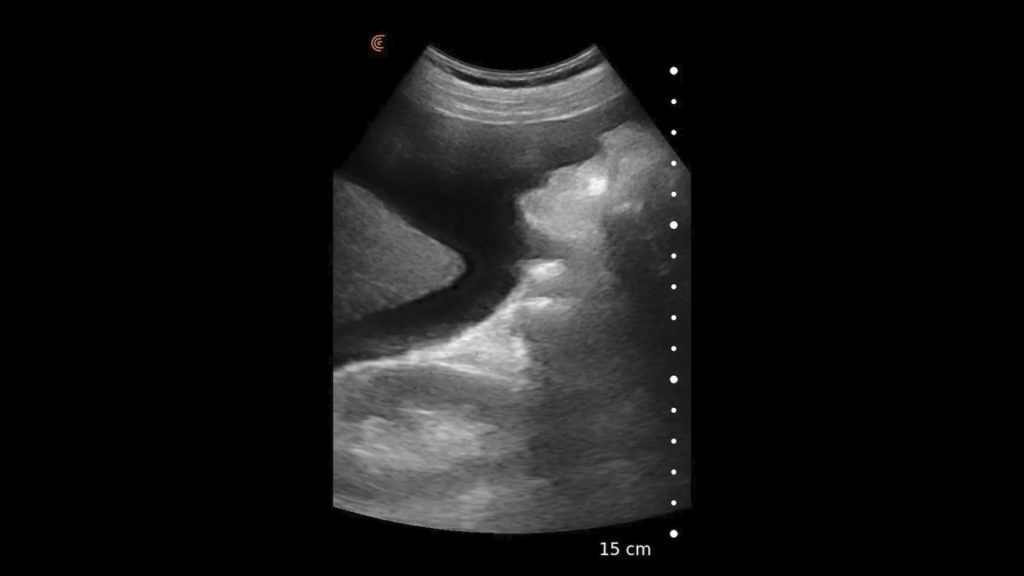

Using the jejunum as an important landmark, the hypoechoic jejunal lymph nodes can be identified. In this video Dr. Edwards explains the ultrasound appearance of normal jejunal nodes.